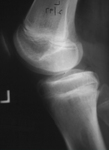

Preoperative radiograph with large osteochondritis lesion of the femoral condyle

From the collection of H. Chambers, MD